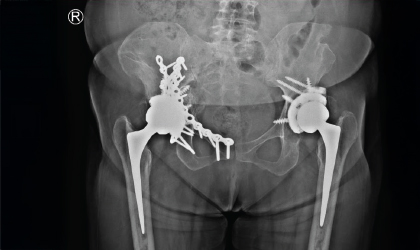

Rheumatoid Arthritis, Conquered

This 54 year old professor from a medical college was referred to us with severe damage to both hips